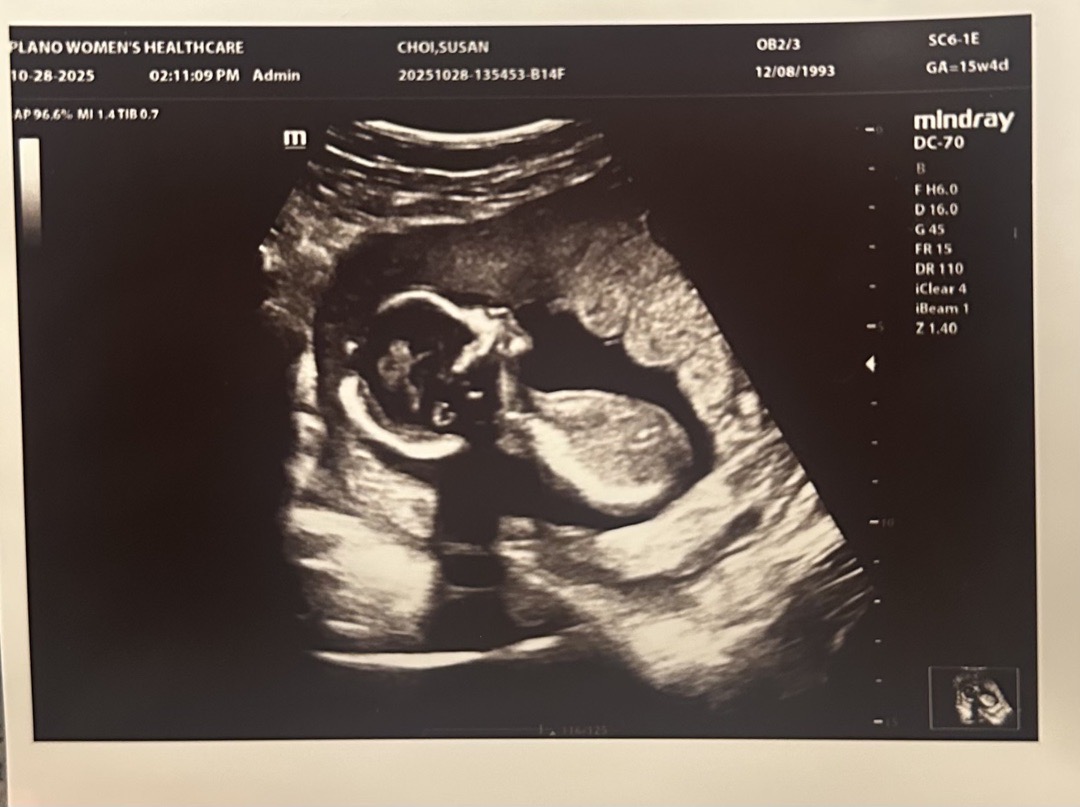

아들일까 딸일까요?

16주 된 맘입니다~ 입덧도 아직까지 있고 과일이랑 매운음식 없으면 못살지만.. 아기가 잘 크고 있다네요 ㅎㅎ 141그램에 크기는 평균보다 큰 편이라는데 아들일지 딸일지 궁금하네요. 아직 결과 나올려면 걸린다고 해서 투표로 알려주세요!🙏🏻